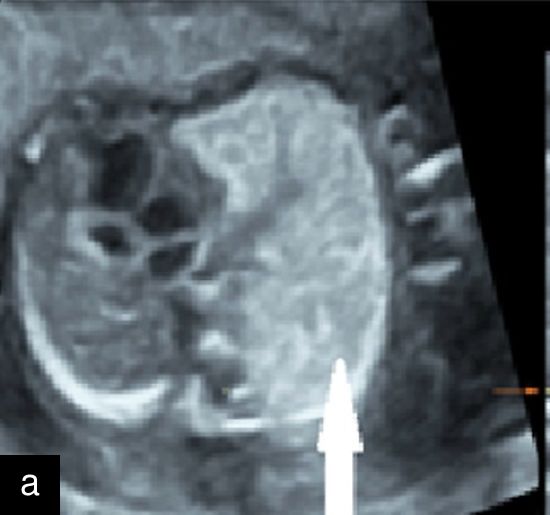

7

(a) Congenital diaphragmatic hernia at 13 weeks with a four-chamber view of the heart (in color) with mediastinal shift and stomach visible in left hemithorax. (b) Congenital diaphragmatic hernia at 20 weeks with a four-chamber view of the heart with the small left ventricle and mediastinal shift, and stomach visible in left hemithorax.